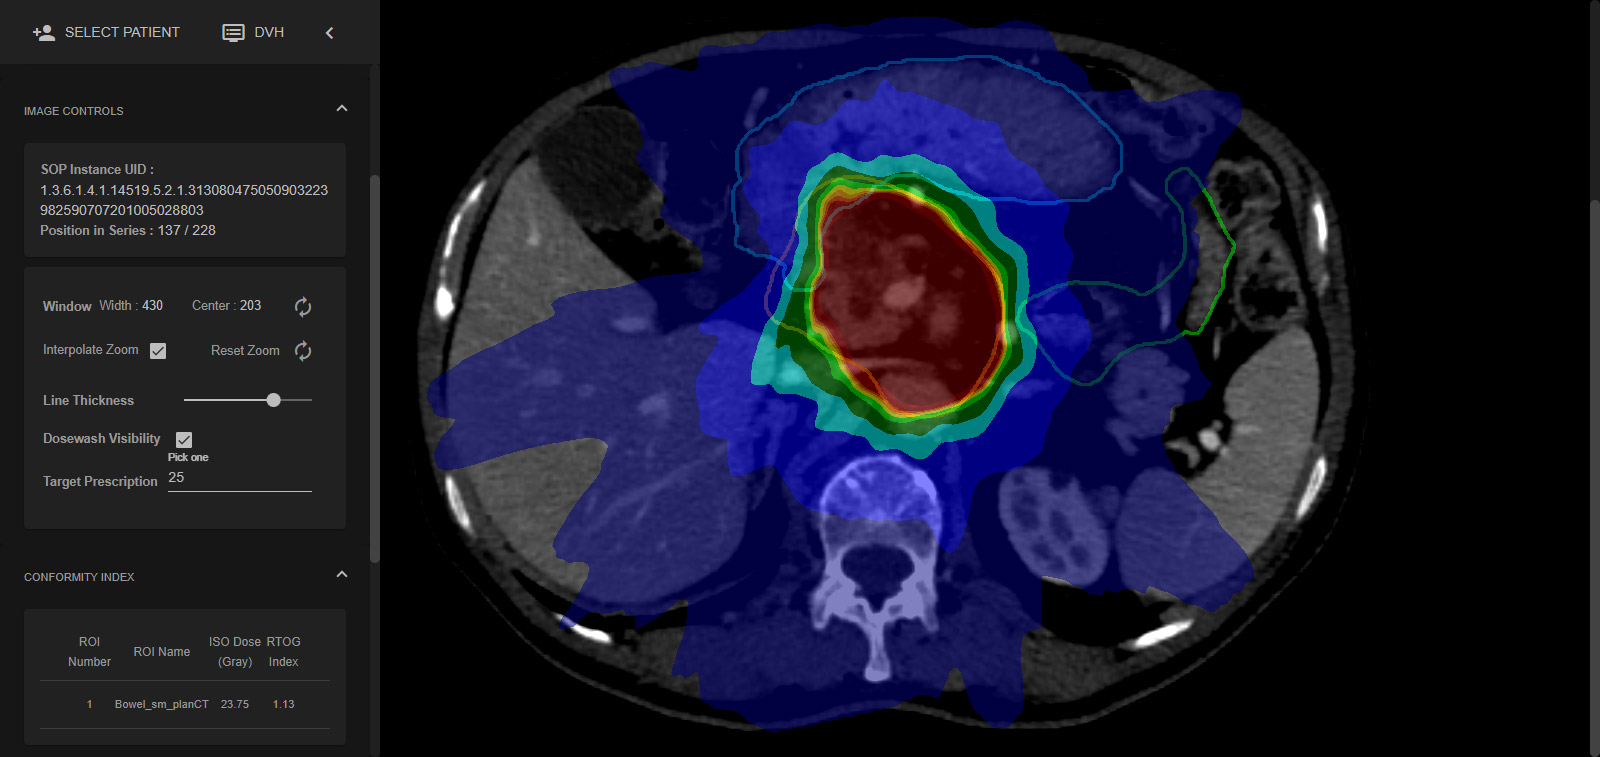

Enhance care with our medical Python Library Rt Dicom Monaco gallery of comprehensive galleries of therapeutic images. medically documenting photography, images, and pictures. designed to support medical professionals. Discover high-resolution Python Library Rt Dicom Monaco images optimized for various applications. Suitable for various applications including web design, social media, personal projects, and digital content creation All Python Library Rt Dicom Monaco images are available in high resolution with professional-grade quality, optimized for both digital and print applications, and include comprehensive metadata for easy organization and usage. Discover the perfect Python Library Rt Dicom Monaco images to enhance your visual communication needs. Our Python Library Rt Dicom Monaco database continuously expands with fresh, relevant content from skilled photographers. Instant download capabilities enable immediate access to chosen Python Library Rt Dicom Monaco images. Diverse style options within the Python Library Rt Dicom Monaco collection suit various aesthetic preferences. The Python Library Rt Dicom Monaco archive serves professionals, educators, and creatives across diverse industries. Regular updates keep the Python Library Rt Dicom Monaco collection current with contemporary trends and styles. Comprehensive tagging systems facilitate quick discovery of relevant Python Library Rt Dicom Monaco content. Time-saving browsing features help users locate ideal Python Library Rt Dicom Monaco images quickly.